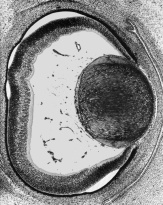

Lens